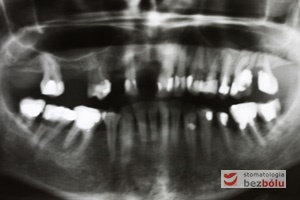

Diagnostyka radiologiczna – ortopantomogram wskazuje zęby nierokujące do usunięcia i liczne wypełnienia do wymiany